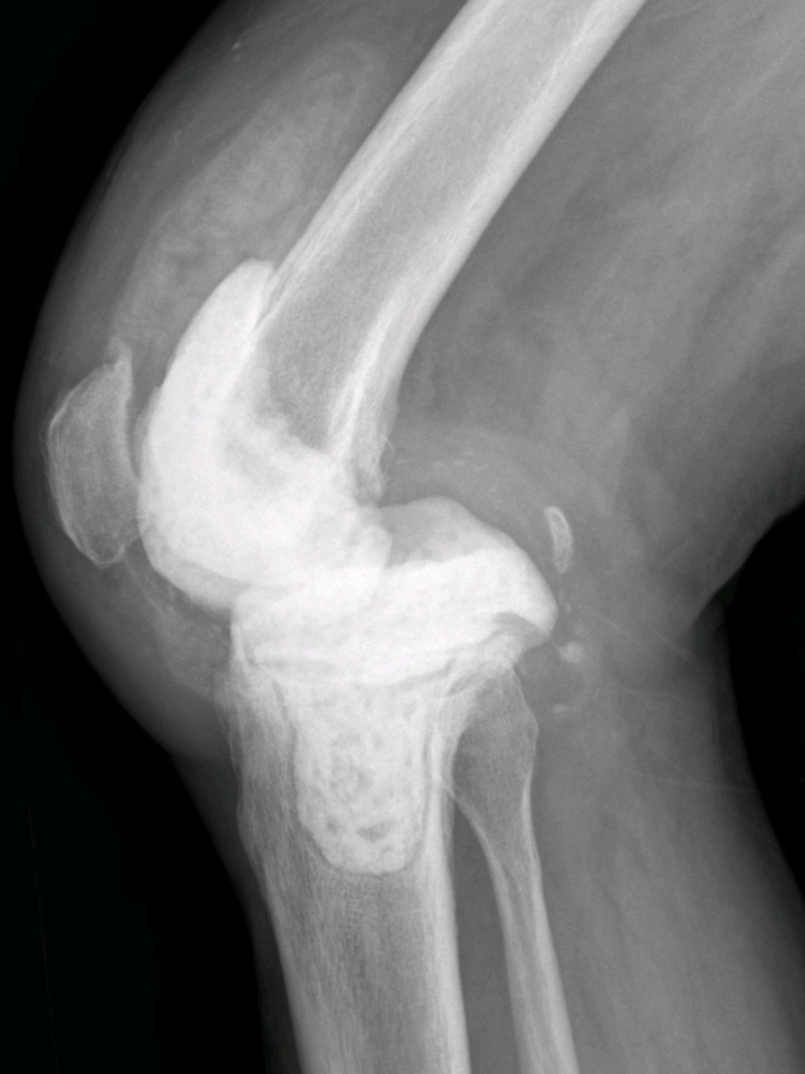

陈大叔两年前进行了全膝关节置换术,术后一年多出现了疼痛、体温高等症状,来院检查后发现是关节置换后感染。关节外科给他做了膝关节旷置术,经过半年多的恢复,查体发现血沉、C反应蛋白等感染指标都已恢复正常。近日,关节外科为其行膝关节翻修手术。

全膝关节假体翻修术前